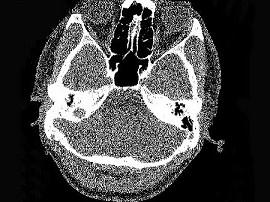

问题 男,23岁,右耳流脓十余年,右外耳道流脓,鼓膜穿孔,CT检查如图,最可能诊断为 ( )

选项 A、嗜酸性肉芽肿 B、(海绵化期)耳硬化症 C、中耳乳突结核 D、中耳癌 E、慢性中耳乳突炎

答案 E